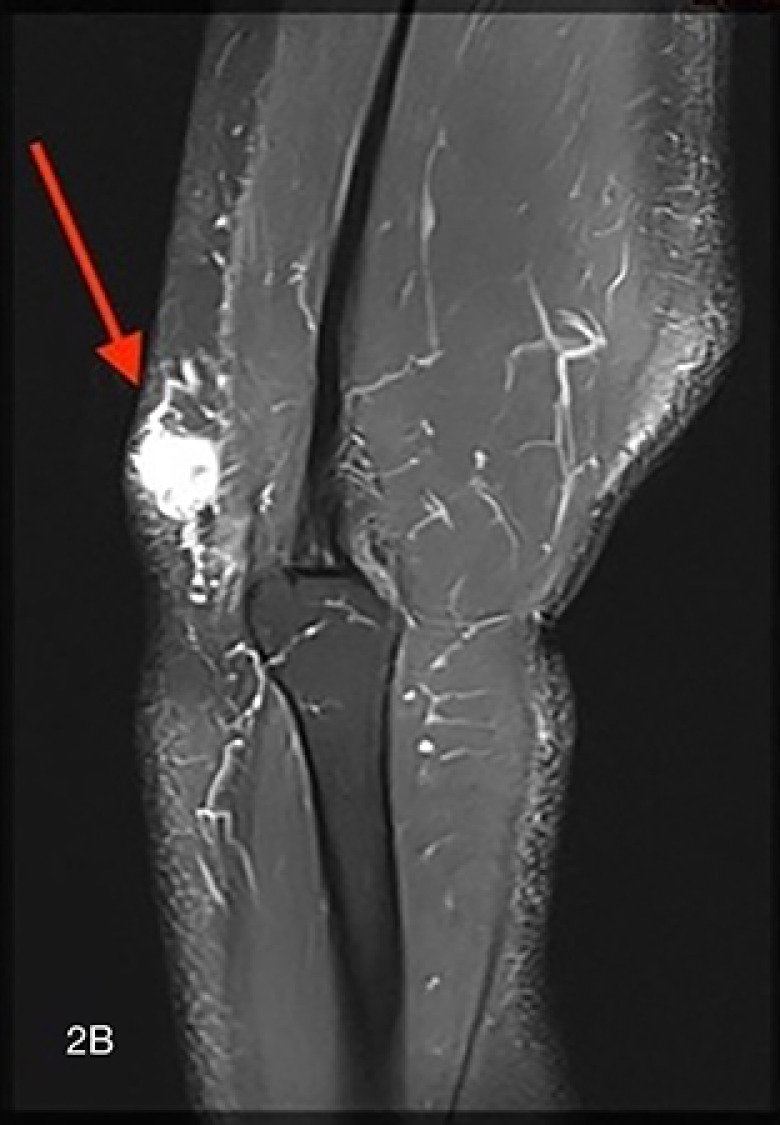

Extradigital Glomus Tumor at the Elbow.

Teaching point: Extradigital glomus tumor should be considered in the differential diagnosis of a highly vascular solid lesion that is painful on palpation.